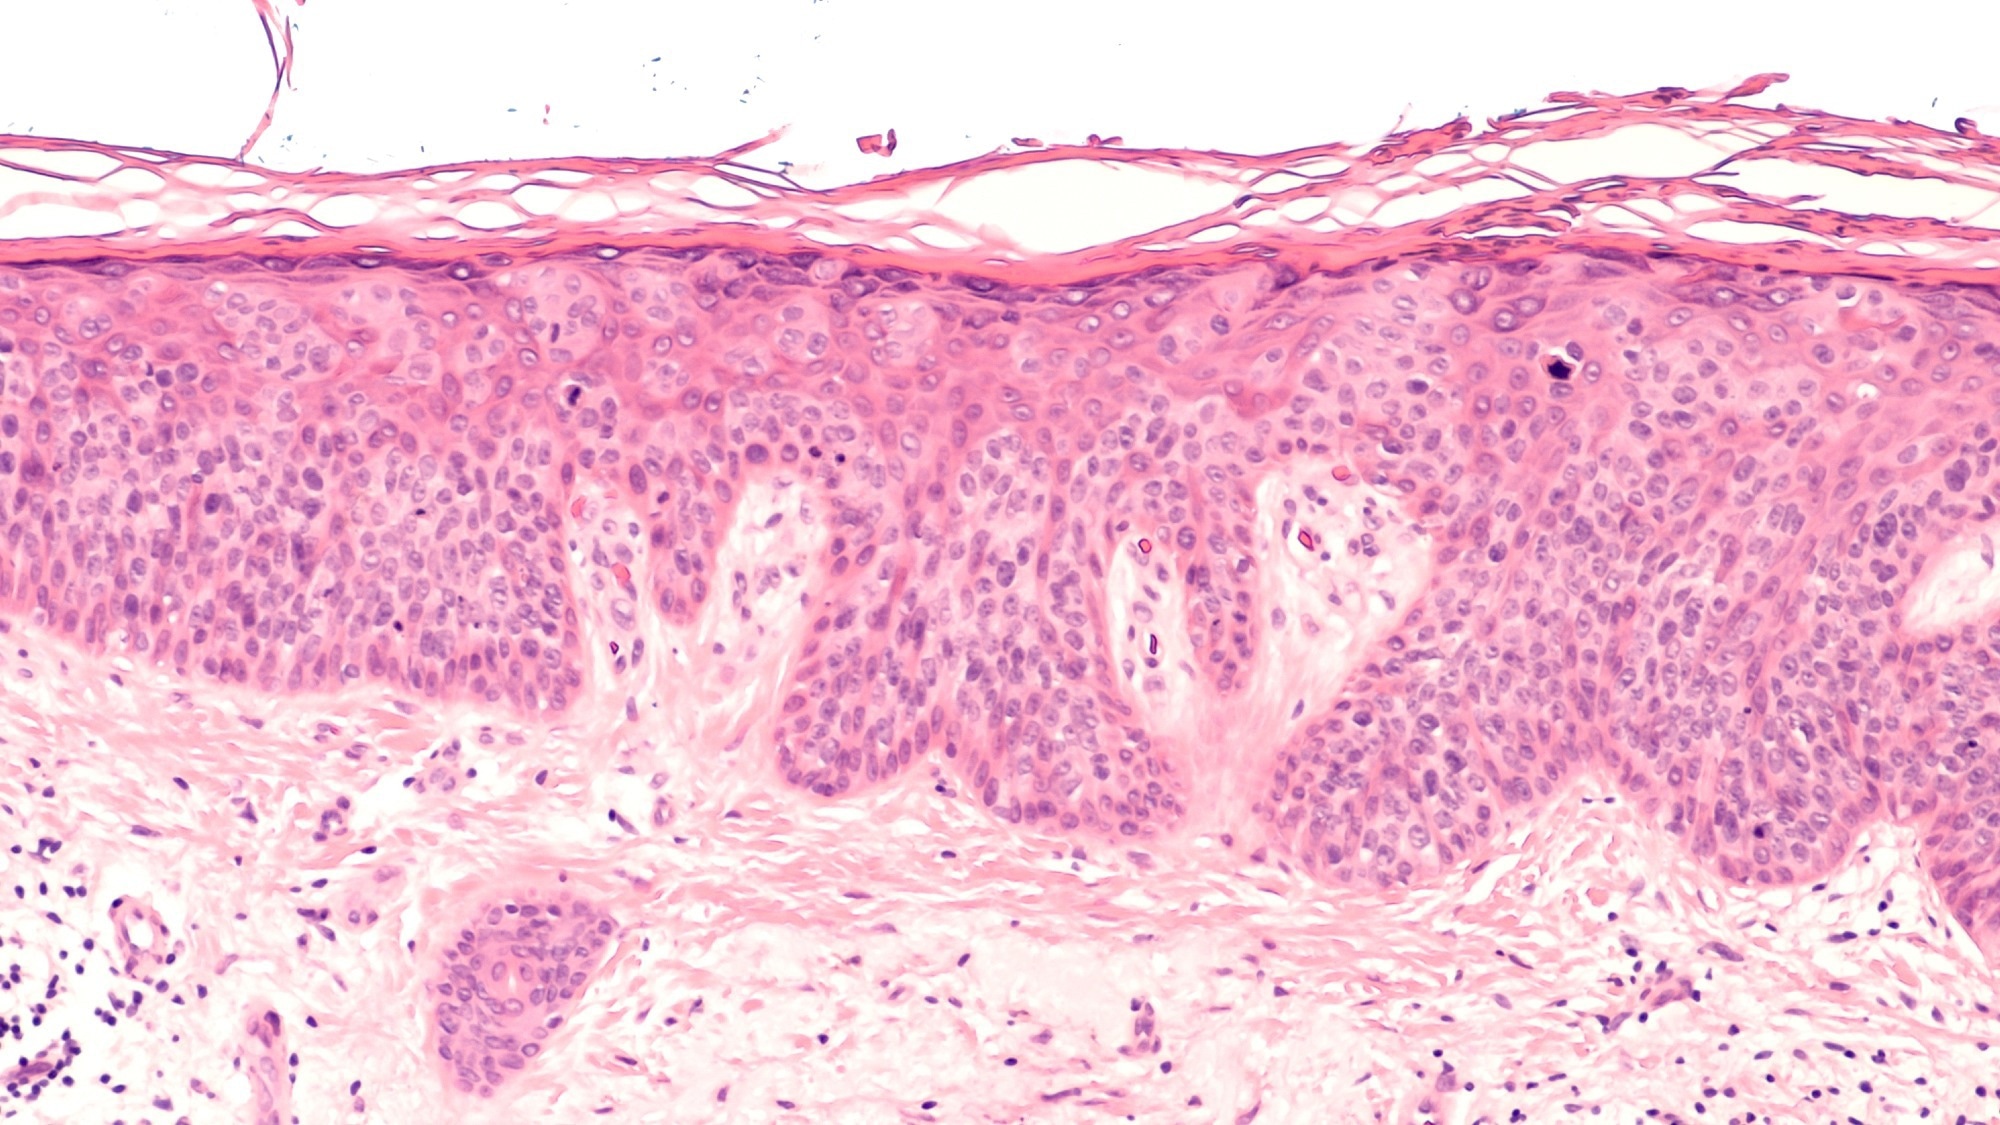

Study: Microfibril-associated protein 5 and the regulation of skin scar formation. Image Credit: David A Litman / Shutterstock.com Study: Microfibril-associated protein 5 and the regulation of skin scar formation. Image Credit: David A Litman / Shutterstock.com

Immunofluorescent staining showed that MFAP5 expression was present in the epidermal and dermal layers in normal skin, wound tissue, and keloid tissue. Furthermore, the epidermal staining of MFAP5 was prominent, thus suggesting the involvement of keratinocytes in the production of MFAP5.